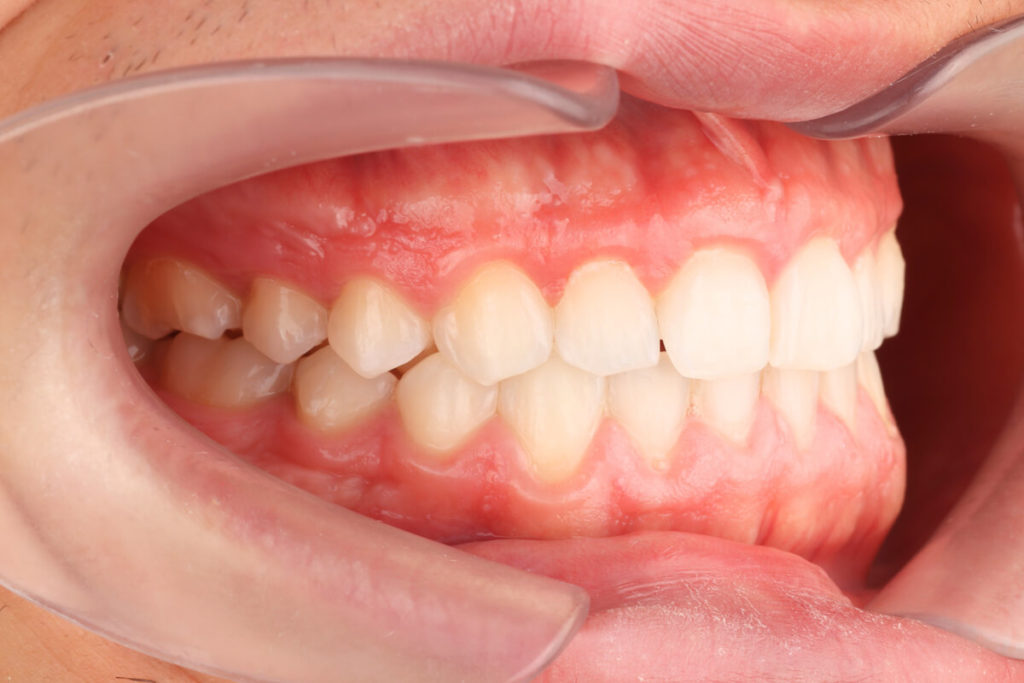

SITUACIÓN INICIAL

CLASE I MORDIDA CRUZADA EN LATERALES

• Clase I con mordida cruzada en los incisivos laterales.

• Apiñamiento moderado en el arco superior e inferior.

• Desplazamiento de la línea media superior.

• Arco normal con necesidad de expansión.